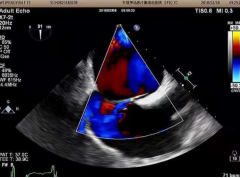

3、經(jīng)食道超聲心動圖及右心聲學(xué)造影

經(jīng)食道超聲心動圖用于精準(zhǔn)評價心臟內(nèi)血栓、卵圓孔未閉的類型及大小、心臟瓣膜損傷、感染性心內(nèi)膜炎等,也便于進(jìn)行心臟手術(shù)中的超聲監(jiān)測與評價,科室近年來在經(jīng)食道超聲心動圖檢查及診斷上積累了豐富的經(jīng)驗(yàn)。

右心聲學(xué)造影可進(jìn)一步提高卵圓孔未閉、房間隔缺損、肺動靜脈瘺、永存左上腔靜脈等異常的超聲檢測率,尤其是不明原因的偏頭痛的病因篩查,科室開展右心聲學(xué)造影數(shù)百例,為偏頭痛的患者查找出了病因,為臨床治療提供了可靠的診斷依據(jù)。